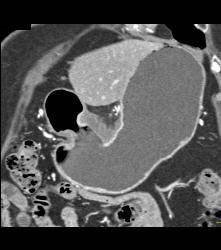

Antral Carcinoma